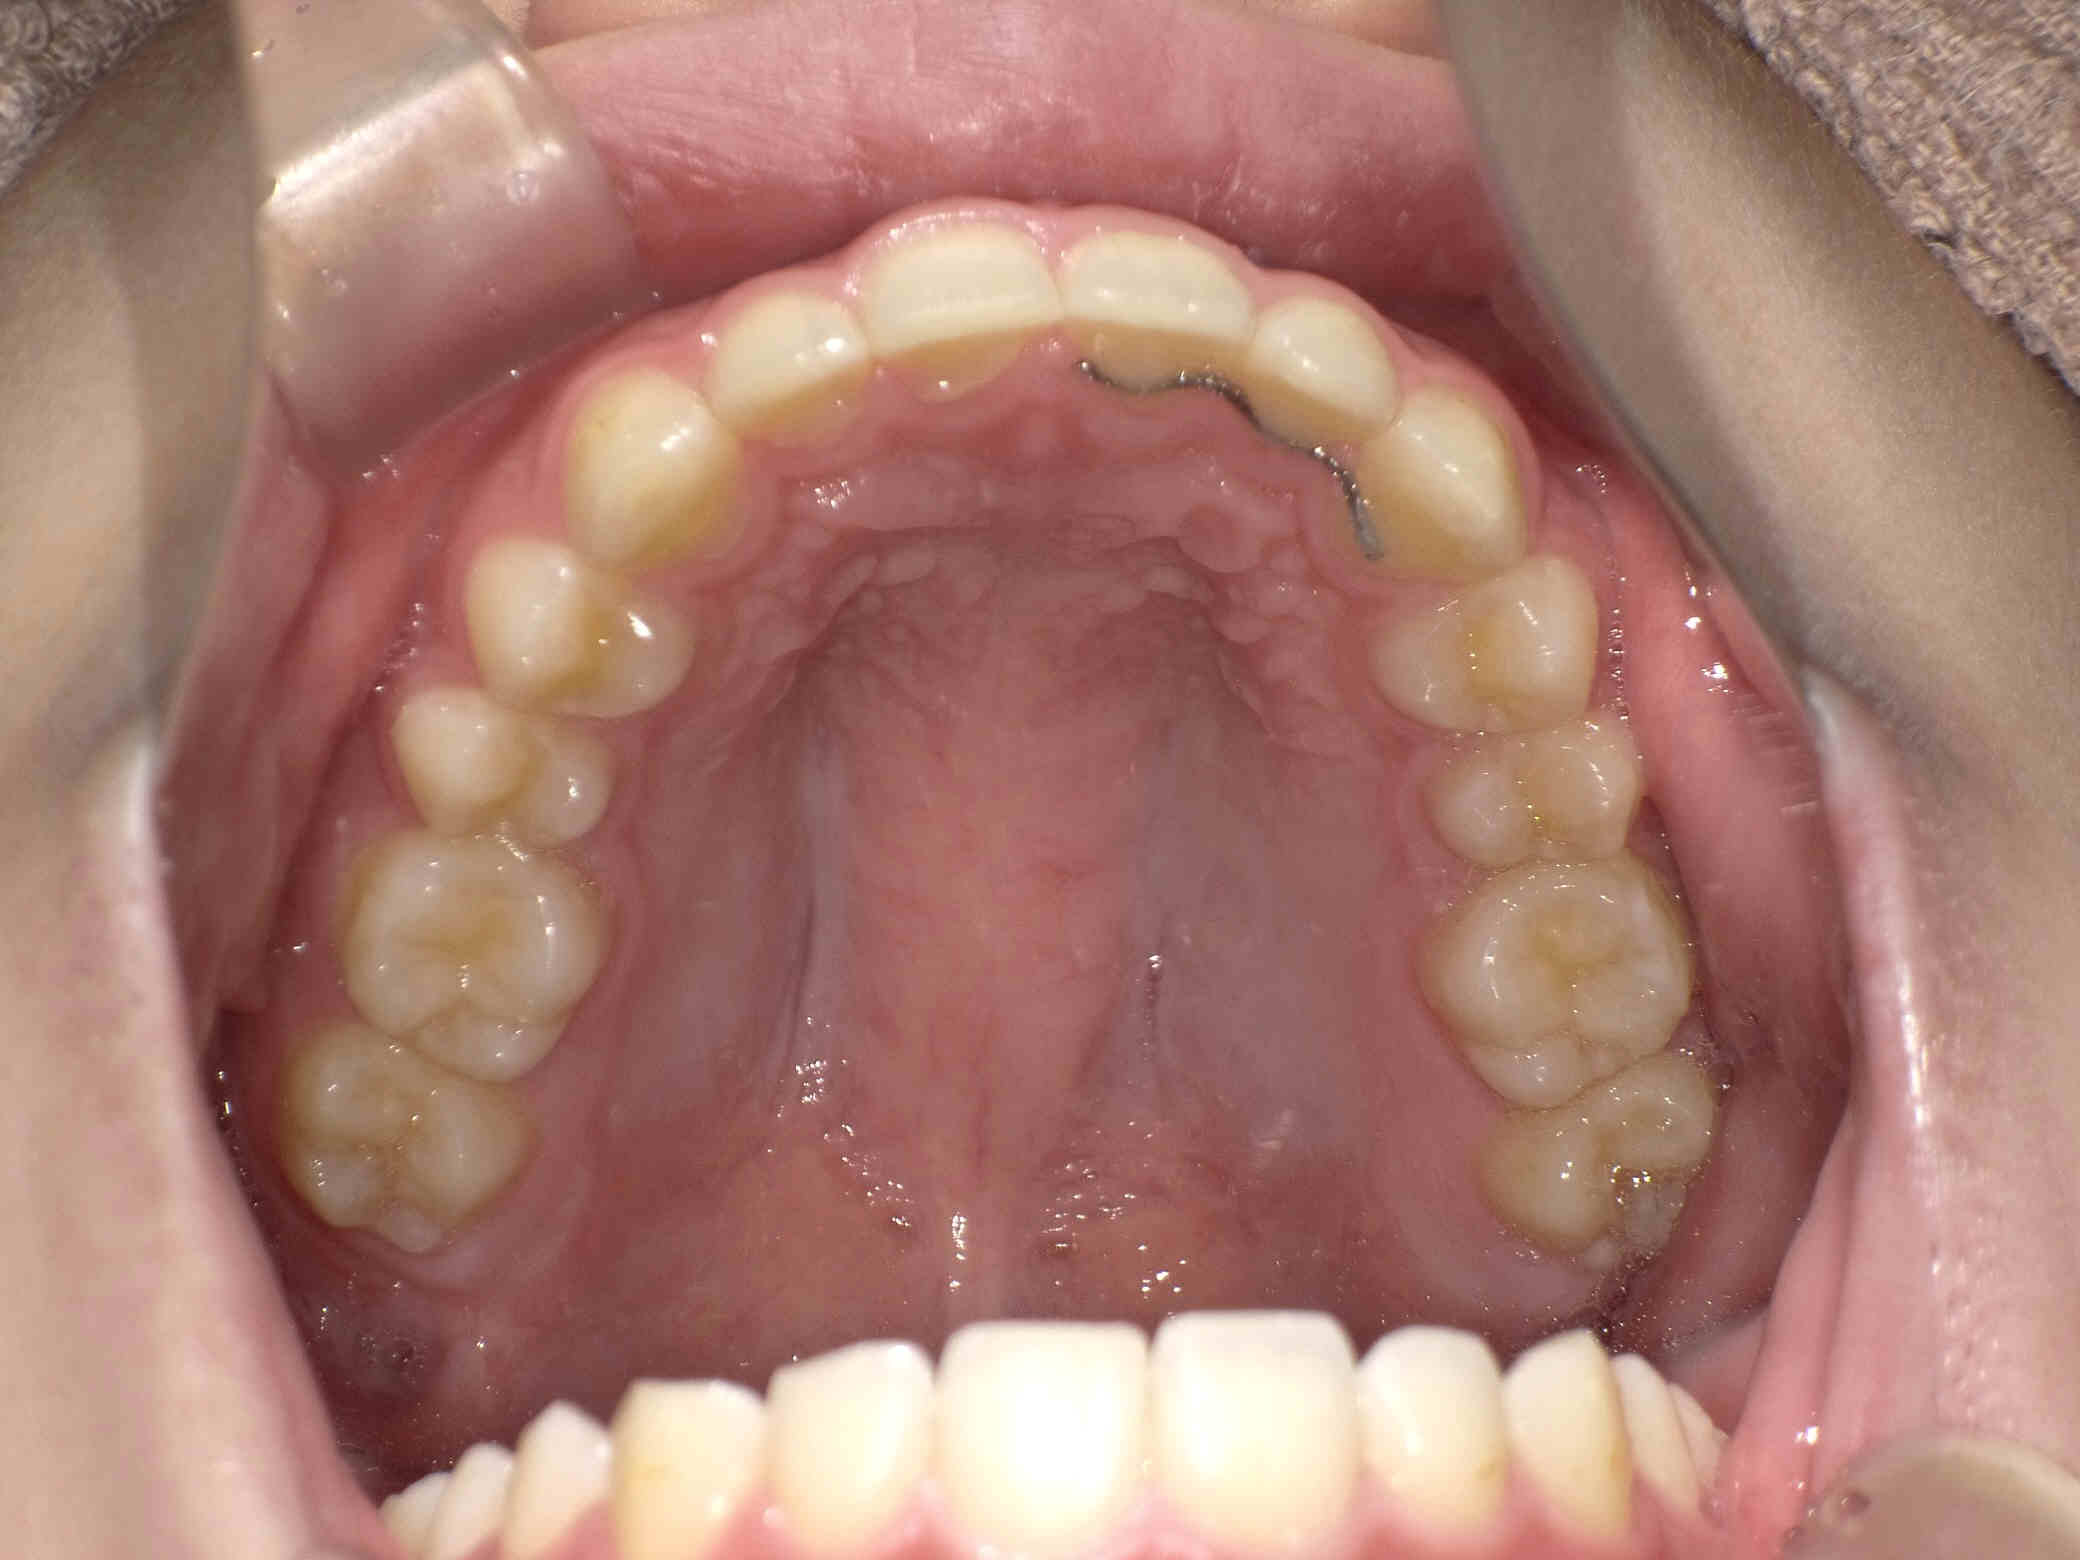

12歳6ヶ月〜スタートです。

やや出っ歯傾向で、噛み合わせが深く

歯並びがデコボコな鋏上咬合(はさみじょうこうごう)という状況でした。

上下の歯がすれ違っている状態で、一部の歯に過度の負担がかかってしまいます。

今回はご希望のワイヤー矯正で治療を行い、スタートから1年半で美しい歯並びに改善しました。